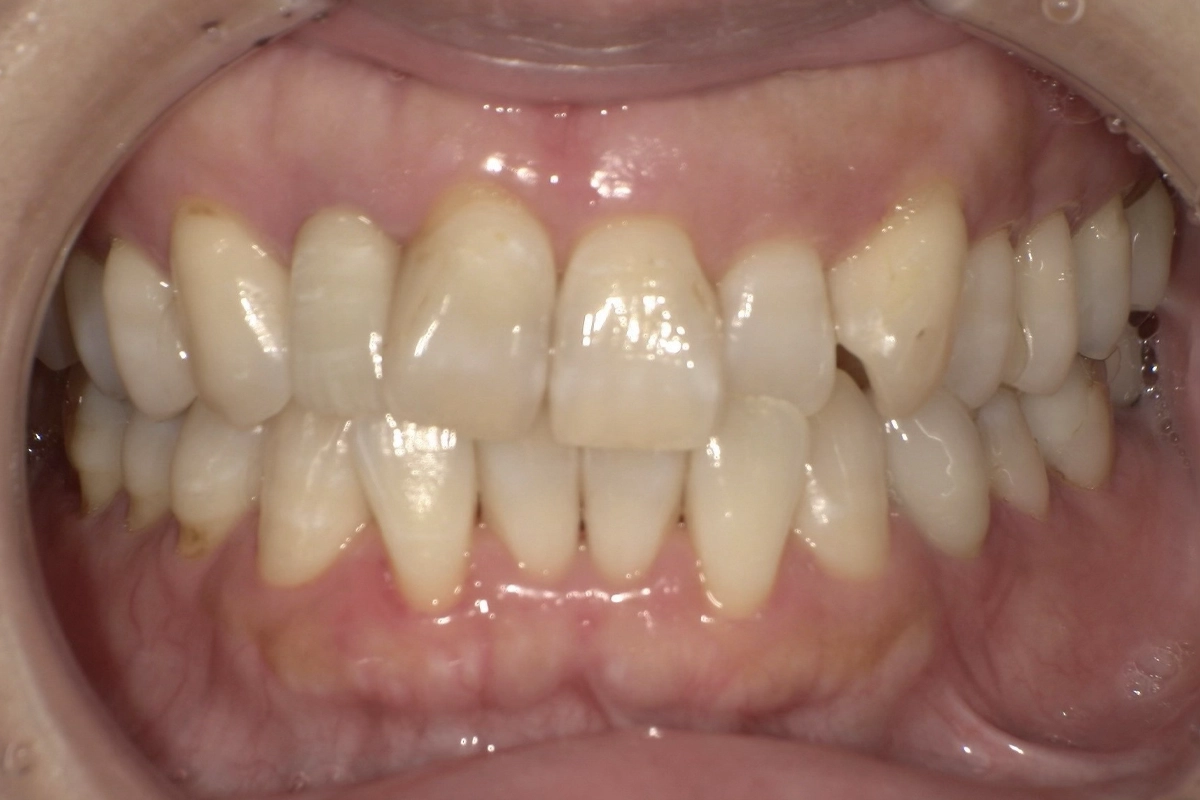

重なり合っていた上下の前歯がきれいに配列され、滑らかなアーチを描く歯並びになりました

正面から見たときの口元の印象が大きく変わり、患者様にも喜んでいただけました。

歯の重なりが解消されたことで、歯ブラシやフロスが隅々まで届きやすくなりました。

治療前に見られた歯石の沈着しやすい環境が改善され、虫歯や歯周病の予防がしやすい状態になっています。